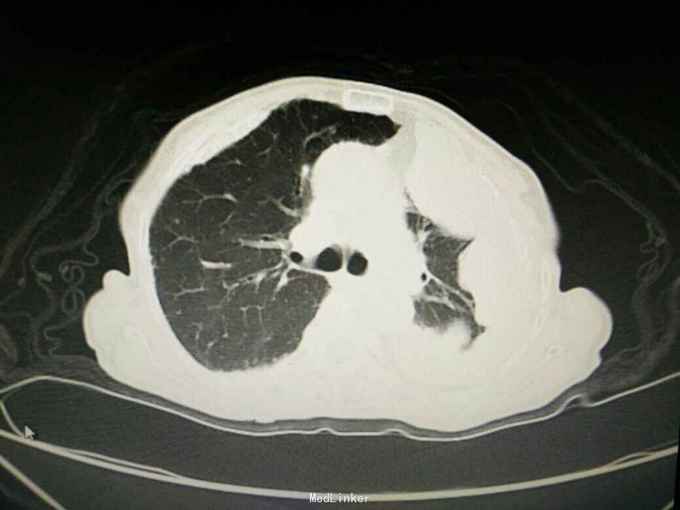

患者陈某某,女,69岁。 主诉:反复咳嗽咳痰1年余,加重伴气促1月。 病史:1年前出现咳嗽咳痰,阵发性,少量白痰,无发热,无盗汗消瘦,无胸闷胸痛,未予重视。1月余前出现咳嗽咳痰加重,伴气促,活动后明显,无夜间阵发性呼吸困难,当地医院胸片示左侧胸膜多发肿块,两侧胸膜增厚钙化,随后至我院就诊。 既往史: 有石棉接触史20余年,40年前行输卵管结扎术,26年前行阑尾切除术,否认其他疾病史,否认烟酒史。

查体:神志清,精神可,生命体征平稳。两肺呼吸音粗,未闻及干湿性啰音。 辅查: 血气分析:PH7.43, 二氧化碳分压43mmHg, 氧分压77mmHg, 氧饱和度95%。 血常规:WBC7.5x10∧9/L, NE77.8%, Hb132g/L, plt231x10∧9/L。 尿常规,粪便常规,凝血功能,肿瘤标志物,CRP, 免疫功能,肝肾功能电解质无明显异常。 痰培养,痰找抗酸杆菌阴性。 心电图无明显异常。 心脏彩超:主动脉瓣局部退行性变,左室舒张功能减退,轻度肺高压。 腹部B超无异常。 胸部增强CT:双侧多发胸膜斑,左侧胸膜弥漫结节状及团块形成,考虑石棉肺伴左侧胸膜继发性恶性间皮瘤可能。

入院诊断:左侧胸膜肿物:胸膜间皮瘤? 诊治经过:予对症支持治疗,行CT引导下胸膜活检 病理:结合免疫组化和临床病史,符合恶性间皮瘤。 治疗:患者明确诊断后予化疗前预处理,择期行培美曲塞+铂类化疗